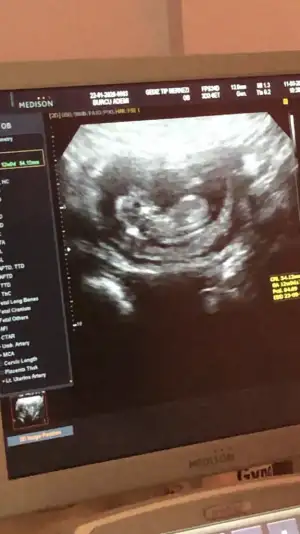

Merhabalar, ctesi ikili test icin gittim 11+6 idim. Suana kadar hep haftayla uyumlu giderdi sat. Ama bu sefer 12+6 cıktım. Yine de cinsiyet yorumlar mısınız? Gec mi kaldım? Bir de doktor tahminini söyledi ama emin değil. Kafanız karışmasın diye en son söyleyeceğim.

Bir de bunu verdi doktor. Sanırım bacak arası ve kenardakiler de bacakları burada. 11+6 idim.